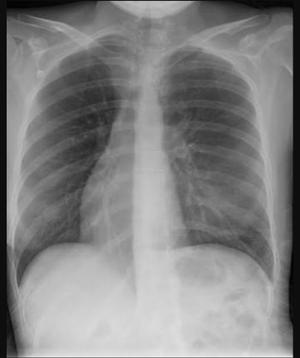

The correct answer is dextrocardia. It is a congenital deformity causing the heart to be on right side. The cause is due to abnormality in the dextrality pathway which is initiated by serotonin at about 3 weeks of gestation. 5HT initiate a cascade of reactions ultimately activating PITX2 gene which is also the master gene of dextrality causing the heart to be on left side. The disruption of this cascade such as hyperthermia (fever during pregnancy) or drugs (mainly affecting the serotonin) results in dextrocardia.